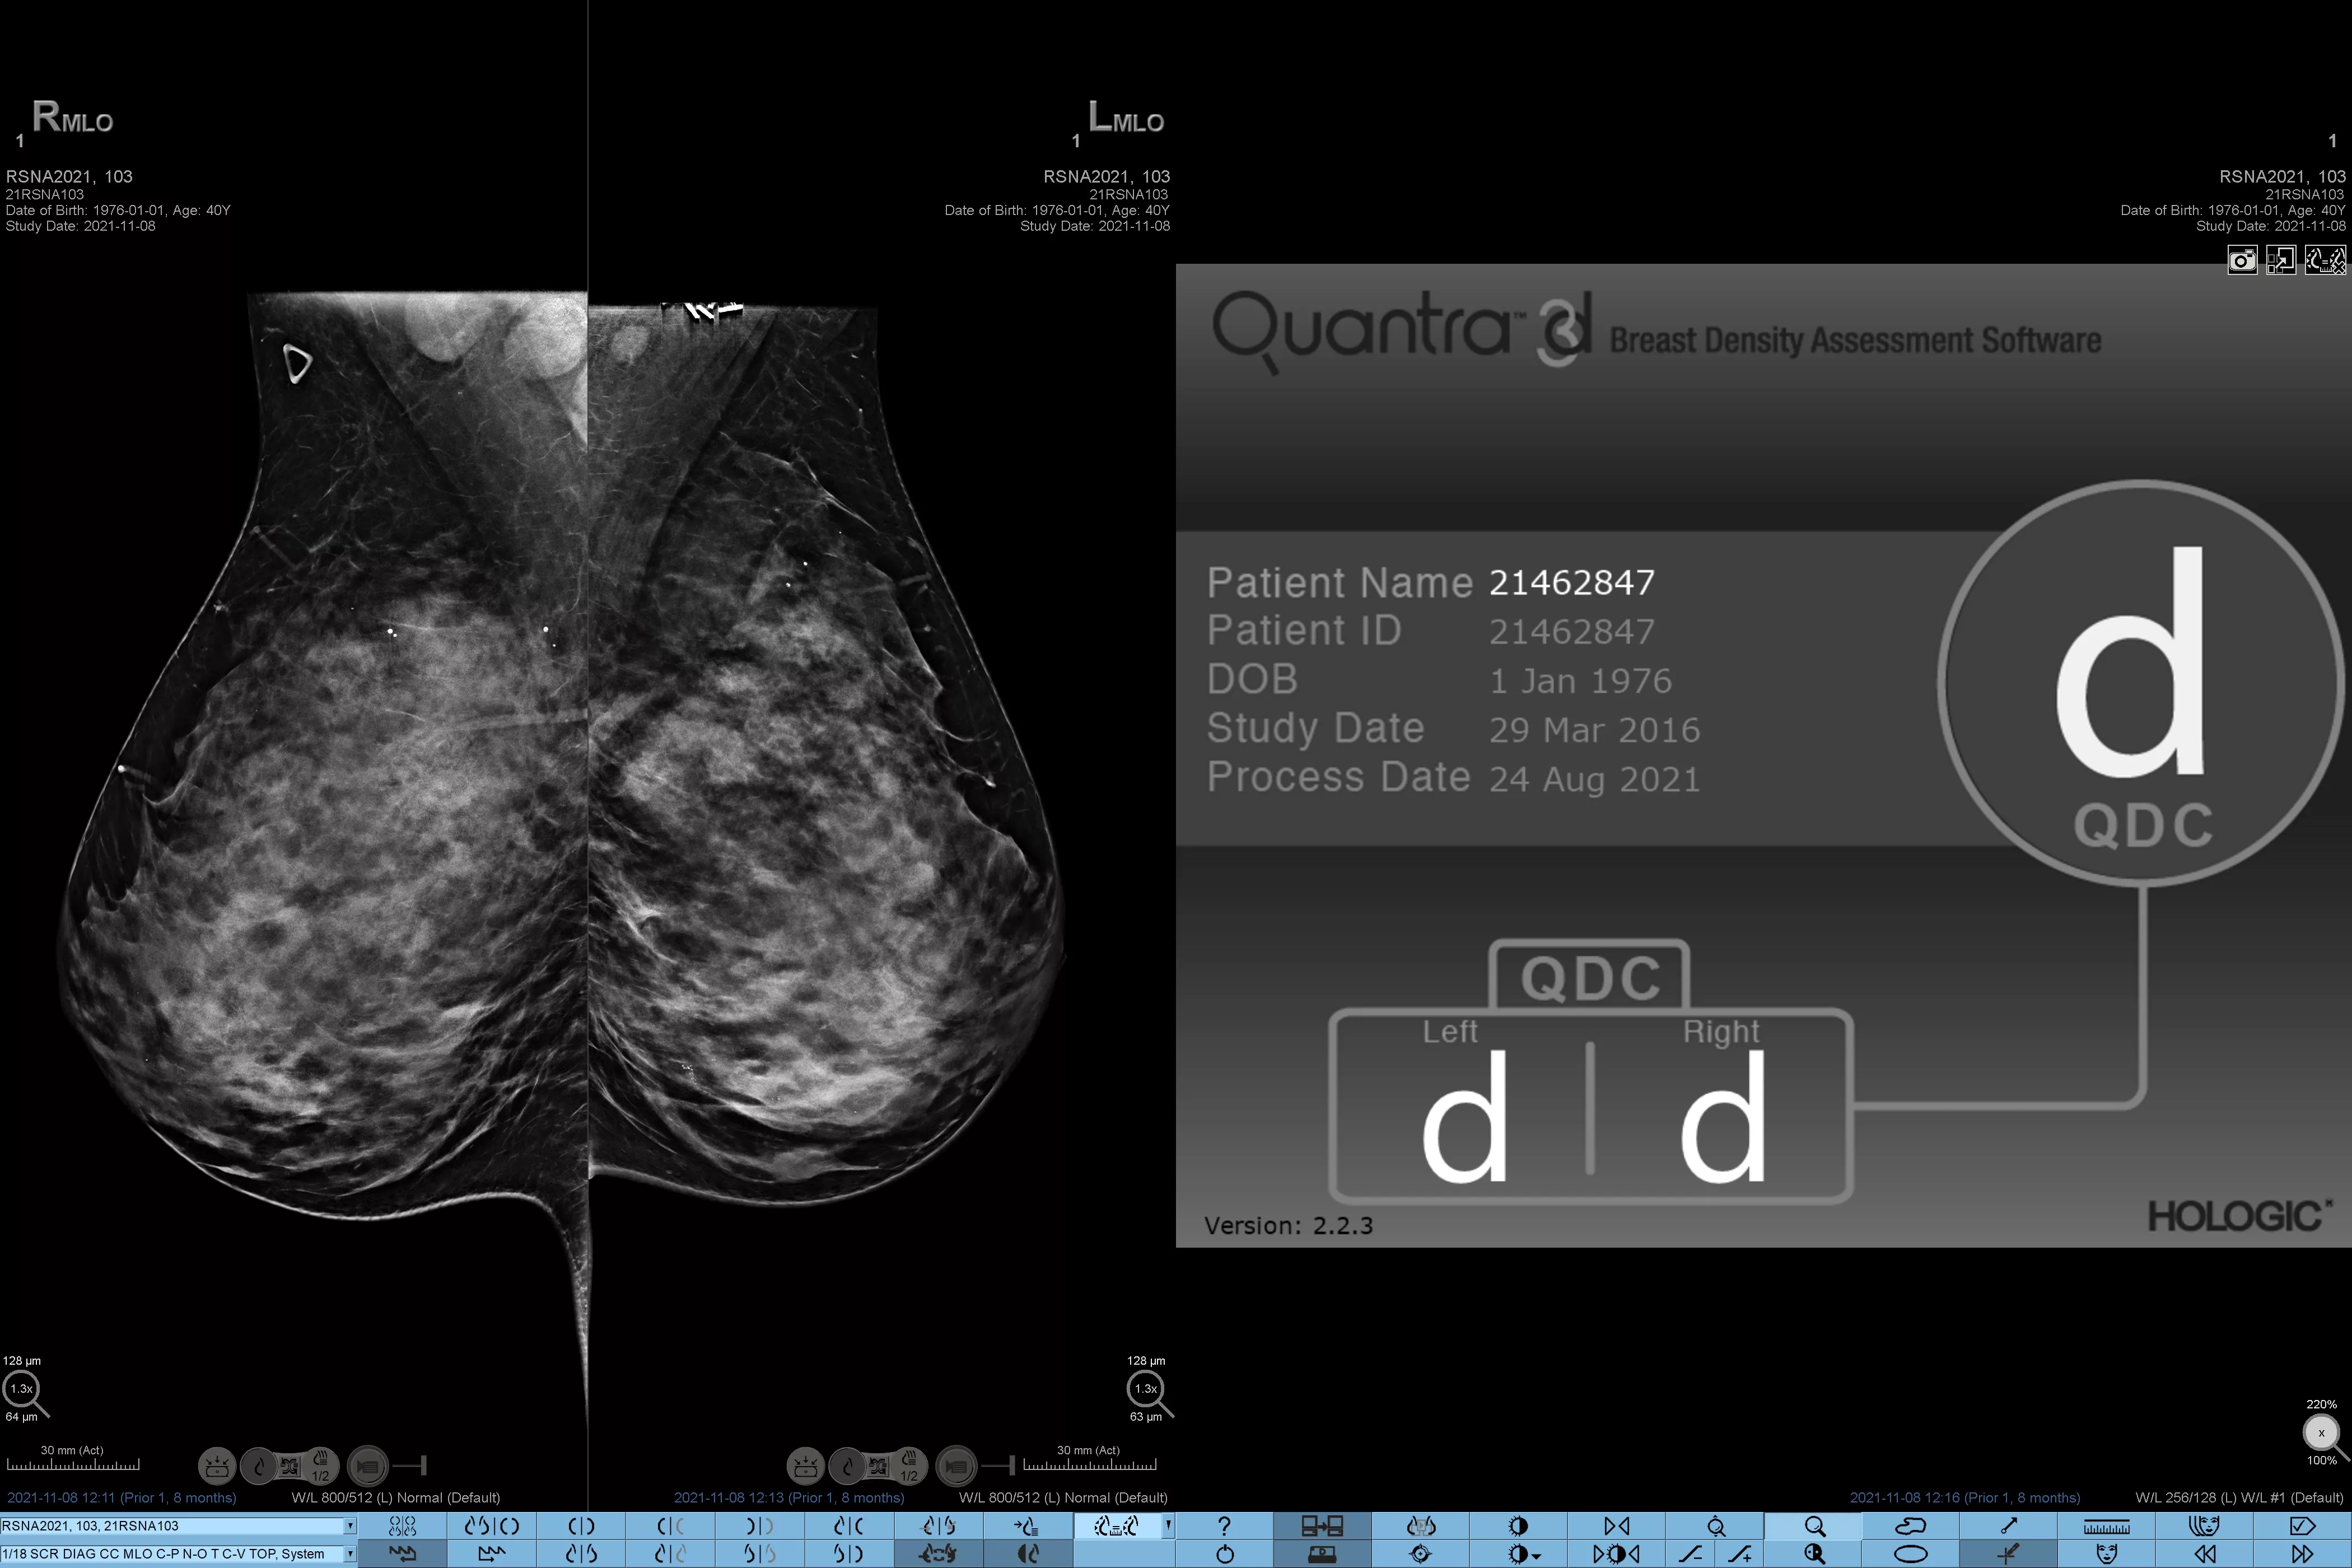

Det är känt att en hög brösttäthet ökar en kvinnas risk för bröstcancer.1 Behovet av noggrann och opartisk analys är därför kritiskt. Med hjälp av maskininlärning analyserar Quantra Technology-programvaran både 2D™- och tomosyntesbilder för fördelning och textur av parenkymal vävnad. Den kategoriserar bröst i fyra bröstkategorier utifrån sammansättning enligt riktlinje från American College of Radiology (ACR) BI-RADS Atlas 5th Edition.2

Objektiv maskininlärningsalgoritm som tilldelar en kategori för brösttäthet baserat på analys av bröstvävnadens textur och mönster.

Den opartiska algoritmen i programvaran analyserar både 2D- och tomosyntesbilder för att:

• Övervinna subjektivitet vid visuell bedömning, vilket ger mer konsekvent och tillförlitlig bedömning*

• Höja vårdstandarden och standardisera rapportering

• Underlätta patienthanteringsprotokoll för kompletterande bilddiagnostik.

* Poängbedömningar baseras på ACR BI-RADS-kategorier enligt de reviderade riktlinjerna från American College of Radiation (ACR) BI-RADS Atlas 5th Edition. Detta motsvarar mönster och textur jämfört med volym vid bedömning av täthet.